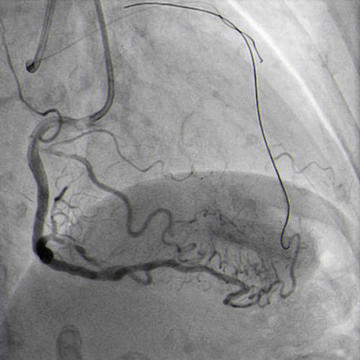

Double radial access with guiding catheter 6F JR 4.0 and sheatless 7.5F PB 3.5. Controlateral injection to check antegrade wire position via collaterals (Figure 4.1).

CTO crossed with Miracle 6g, after unsuccessful attempts with Sion and Pilot 150. Floppy wire in diagonal branch to improve support (Figure 4.2).